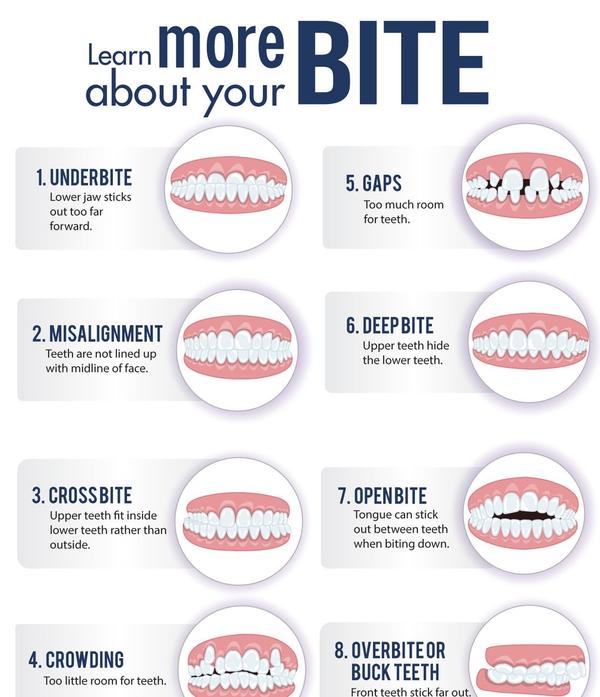

Best dentist near me | Learn More About Your Bite ...

View Details